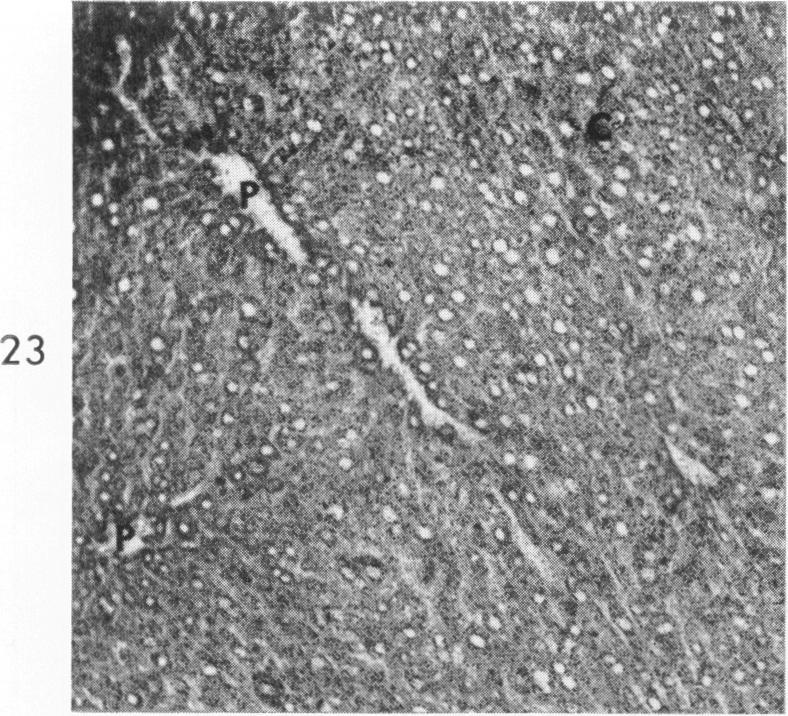

STUDIES ON NECROSIS OF MOUSE LIVER IN VITRO: ALTERATIONS IN SOME HISTOCHEMICALLY DEMONSTRABLE HEPATOCELLULAR ENZYMES.

GOLDBLATT P J, TRUMP B F, STOWELL R E

Am J Pathol. 1965 Aug;47(2):183-208.